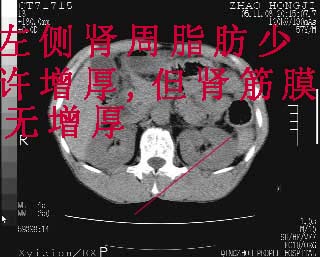

肝脏前缘见少量积气、胰尾部见少许气体包饶,肾前筋膜未见增厚,临床淀粉酶不高,意见:上消化道穿孔。